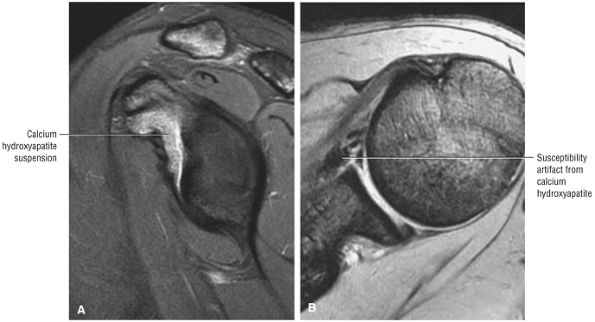

matrix and longer echo time (TE) values. To maximize signal-to-noise in FS PD-weighted FSE images, TE values are usually between 40 and 50 msec and repetition times (TRs) are between 3000 and 4000 msec. These parameters provide adequate coverage and maximum signal-to-noise. We do not use T2*-weighted coronal oblique images to evaluate the rotator cuff. Although GRE techniques adequately demonstrate bursal and articular cuff outlines, areas of increased signal intensity may be seen in both cuff degeneration and tears, making the distinction between tendinopathy or tendinosis and rotator cuff tear difficult. T2*-weighted axial images are, however, used to evaluate the glenohumeral capsule and labrum, at a FOV of 10 cm. GRE techniques provide good visualization of intralabral degeneration and tears, whereas FS PD FSE images are more sensitive to paralabral cysts and the articular cartilage labral interface. Magnetic susceptibility artifacts (signal void) are prominent with GRE techniques, especially when evaluating the postoperative shoulder. This susceptibility may be useful in identifying loose bodies or foci of calcific tendinitis. Coronal plane images are also used to quantify the medial-to-lateral dimension of a rotator cuff tear.

T2* GRE images (10-cm FOV) are used to evaluate intralabral pathology, subscapularis tendinosis, and calcific tendinitis (Fig. 8.3).